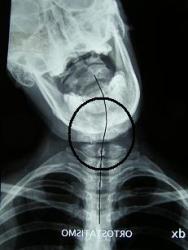

Le immagini che vedete sono fatte in flessione laterale massima, proprio per vedere cosa si muove e cosa no. Le linee collegano due vertebre e in una situazione normale dovrebbero disegnare un arco, una curva dolce e armonica. Invece potete vedere che ci sono un po’ di zig zag.